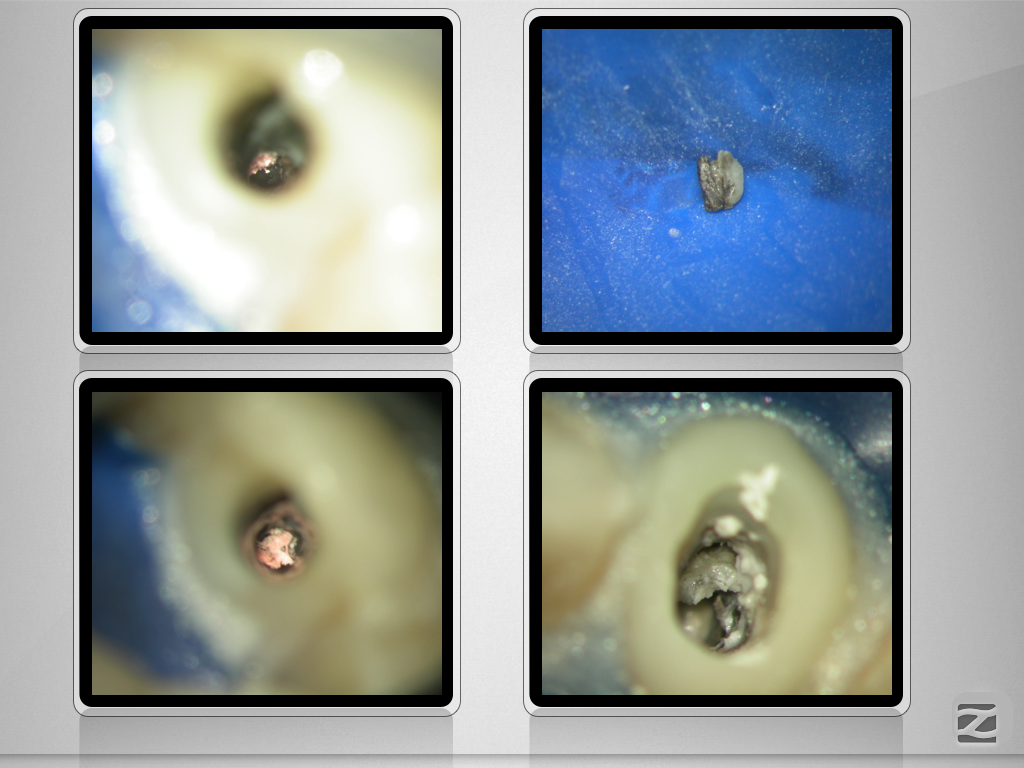

Kurioses Leakage